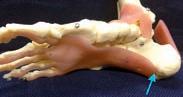

Cancer experts are trying to change the narrative on the unwanted side effects from prostate cancer treatment.

It was once the inevitable collateral damage from prostate cancer treatment – the lifechanging side effects that were considered the price that men had to pay to beat the disease.

Incontinence and erectile dysfunction (ED) have often been the unwanted legacy of radical surgery and radiation treatment, associated with poor rates of recovery.

That includes innovative rehabilitative techniques and penile implants, as well as a new technique which has been used in Melbourne to restore erectile function by removing sural nerves from the patient’s leg and grafting them for use in the penis.

It is also difficult to get a full picture of the prevalence of ED in men post-prostate cancer treatment, partly because some men do not report symptoms or seek help, but it is estimated to affect between

Dr Sofield told Medical Forum that there has not been major progress over the years in preserving erectile function after prostate cancer treatment – be it radiation or surgery.

Both had very high rates of causing erectile dysfunction, and to a lesser extent incontinence.

However, Dr Sofield said there were now good treatments available to restore sexual health, with multidisciplinary rehab programs for men after surgery, using nonsurgical treatment.

“And at the end of that process, if conservative options fail, one to two years after surgery, then they might come back and we look at the last option, which is a surgical implant.

“The uptake of those is increasing but is still relatively low because a lot of men and their partners are willing to go so far, but for some of them that’s a step too far and they decide if that’s what it’s going to take, they’ll probably just let it go.